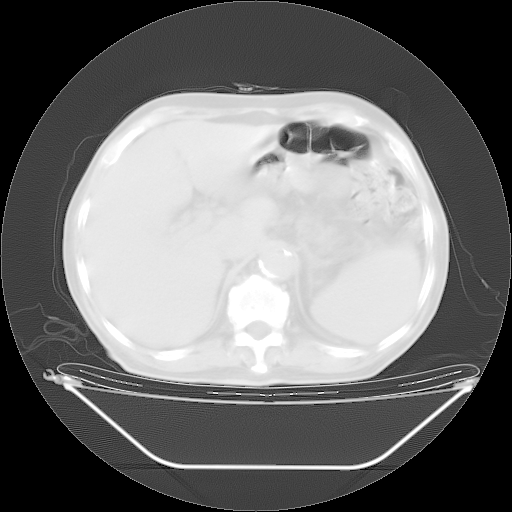

胸腹部CT,诊断意见:左上肺叶钙化灶、左侧胸膜局限性增厚并钙化、胆囊炎。描述部分肺组织呈磨玻璃样改变。